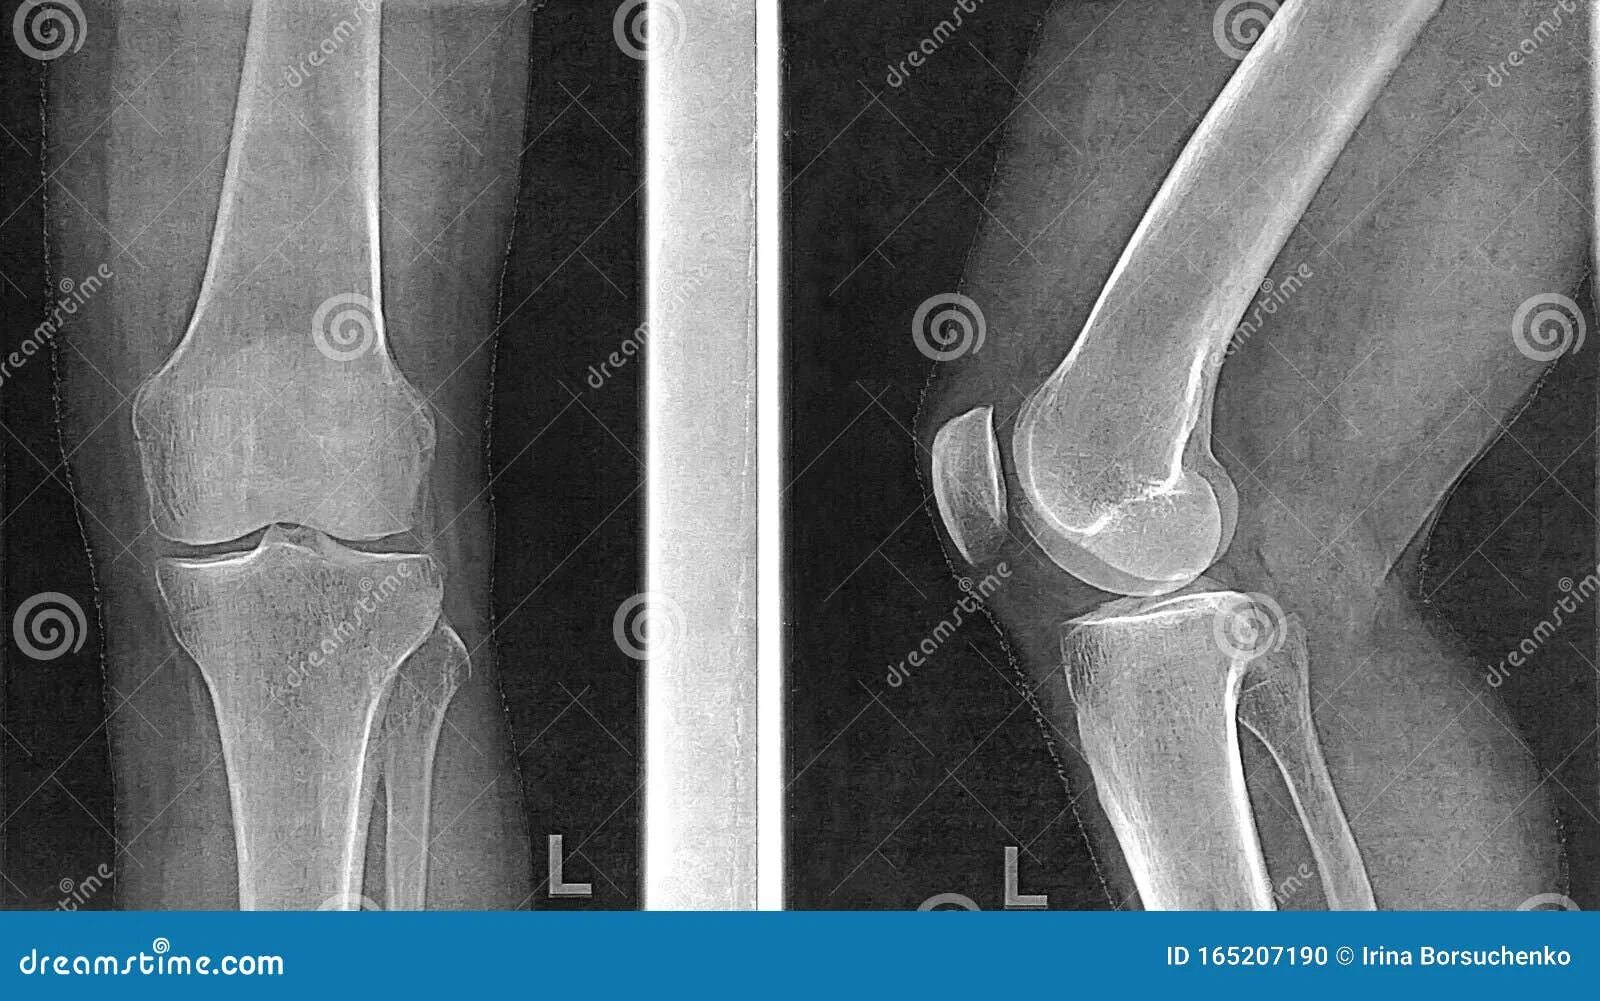

Рентгенография коленного сустава 2 проекции